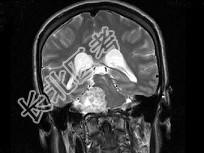

- 单项选择题女,45岁, 右侧听力下降伴行走不稳2个月,根据所提供图像, 最可能的诊断是 ( )

A、右侧脑膜瘤

B、右侧胆脂瘤

C、右侧皮样囊肿

D、右侧神经纤维瘤

E、右侧听神经瘤